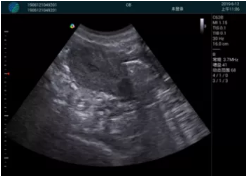

清晰顯示孕囊,通過(guò)軟件包計(jì)算孕齡7w+6d

M20實(shí)時(shí)引導(dǎo),術(shù)中清晰顯示孕囊被破壞和抽吸針的過(guò)程,清晰顯示吸引針

抽吸結(jié)束后縱切子宮,孕囊已被完全抽吸,未見(jiàn)明顯殘留

橫切子宮,發(fā)現(xiàn)右側(cè)宮腔靠近宮角處有少許脫模樣殘留

M20引導(dǎo)下,抽吸針找到右側(cè)宮角處再次清掃

二次抽吸后再次進(jìn)行超聲檢查,宮腔未見(jiàn)殘留,宮腔線清晰顯示